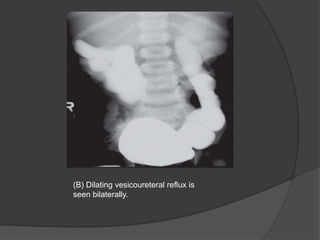

(B) Dilating vesicoureteral reflux is

seen bilaterally.

(A) Voiding cystourethrogramimage demonstrates a dysmorphic, elongated bladder with dilated posterior urethra and classic appearance of posterior urethral valves.

• 45.

(B) Dilating vesicoureteralreflux is seen bilaterally.